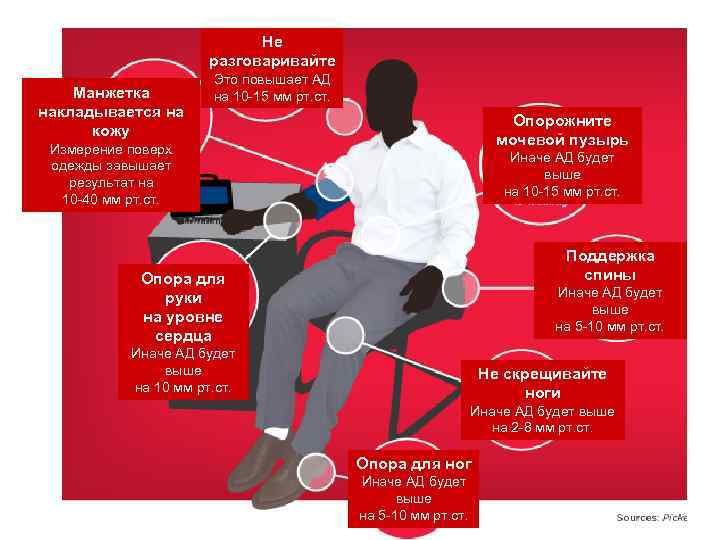

Не разговаривайте Манжетка накладывается на кожу Это повышает АД на 10 -15 мм рт. ст. Опорожните мочевой пузырь Измерение поверх одежды завышает результат на 10 -40 мм рт. ст. Иначе АД будет выше на 10 -15 мм рт. ст. Поддержка спины Опора для руки на уровне сердца Иначе АД будет выше на 5 -10 мм рт. ст. Иначе АД будет выше на 10 мм рт. ст. Не скрещивайте ноги Иначе АД будет выше на 2 -8 мм рт. ст. Опора для ног Иначе АД будет выше на 5 -10 мм рт. ст.

Не разговаривайте Манжетка накладывается на кожу Это повышает АД на 10 -15 мм рт. ст. Опорожните мочевой пузырь Измерение поверх одежды завышает результат на 10 -40 мм рт. ст. Иначе АД будет выше на 10 -15 мм рт. ст. Поддержка спины Опора для руки на уровне сердца Иначе АД будет выше на 5 -10 мм рт. ст. Иначе АД будет выше на 10 мм рт. ст. Не скрещивайте ноги Иначе АД будет выше на 2 -8 мм рт. ст. Опора для ног Иначе АД будет выше на 5 -10 мм рт. ст.